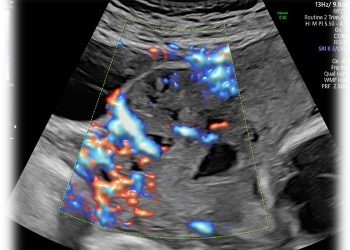

How To Do Febbraio 2024: Istmocele

Cari soci, questo mese un nuovo video "How to do", dedicato allo studio ecografico dell'istmocele Grazie a Daniela Giuliani! Il...